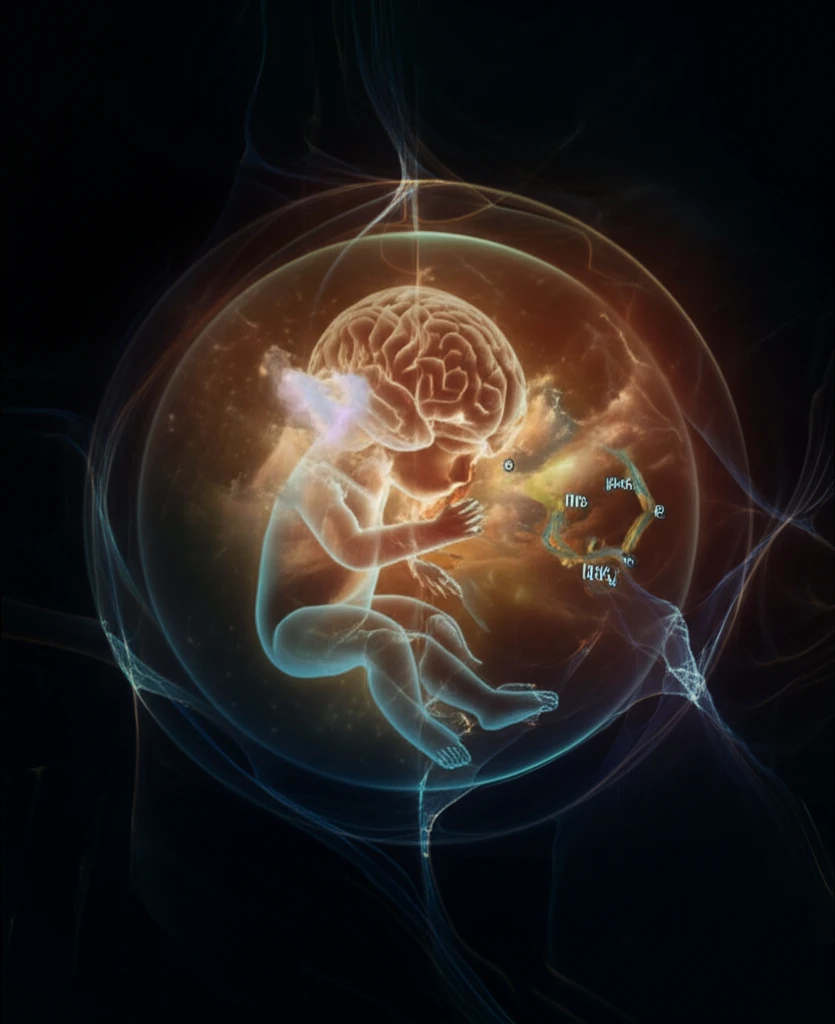

Neonatal Brain Protection: How Myeloid Cell Signaling Can Prevent Hypoxic Ischemic Encephalopathy

Neonatal hypoxic-ischemic encephalopathy (HIE) is a devastating condition that results in long-term motor and cognitive impairments in children. This occurs when the brain doesn't receive enough oxygen, often during birth, leading to significant brain damage. Understanding how to protect the delicate neonatal brain during such crises is crucial.

Recent studies have shed light on the critical role of the immune system, particularly myeloid cells, in either exacerbating or mitigating brain injury following HIE. These immune cells, including microglia and monocytes, can release substances that either protect the brain or worsen the damage. One key player in this process is a protein called interferon regulatory factor 4 (IRF4).

New research indicates that IRF4 signaling in myeloid cells may hold the key to protecting neonatal brains from HIE. By exploring this pathway, scientists are uncovering potential therapeutic targets to prevent or reduce the severity of brain damage in newborns at risk.